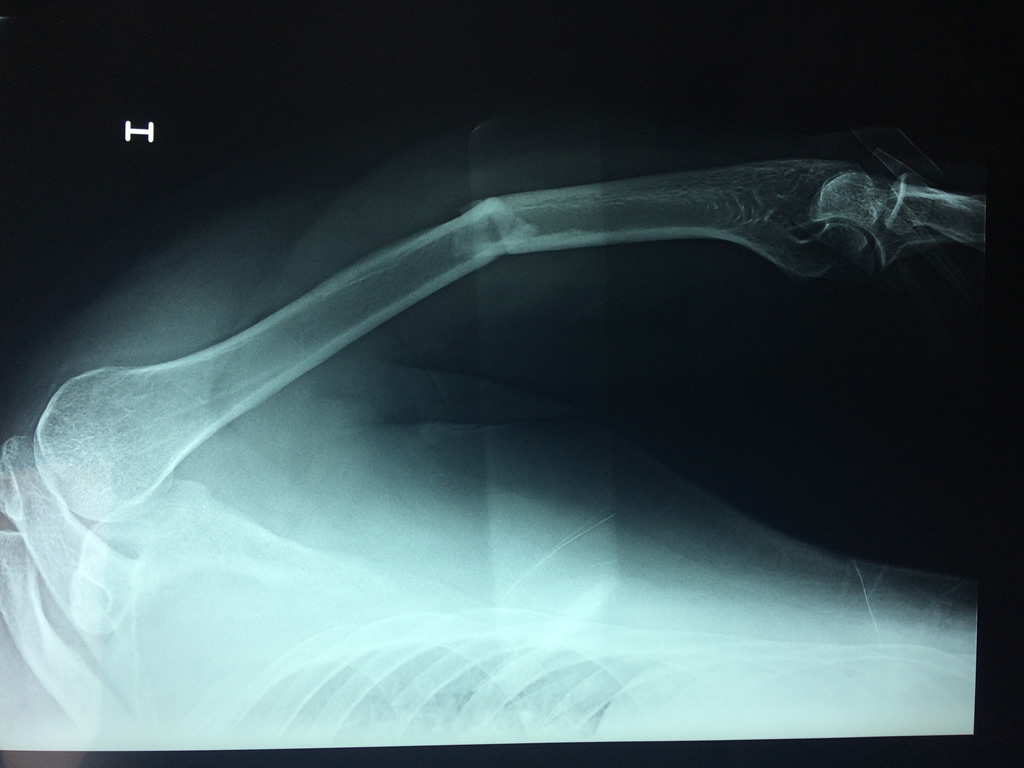

Húmero - Húmero

El Húmero (en latín, humerus) es el hueso más largo de las extremidades superiores en el ser humano. Forma parte del esqueleto apendicular superior y está ubicado en la región del brazo. ... El extremo proximal del húmero tiene la cabeza, cuellos quirúrgico y anatómico y tubérculos mayor y menor.